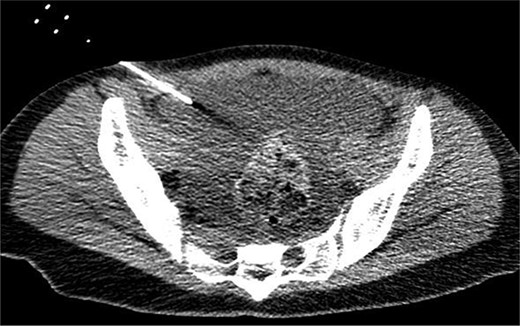

CT of the pelvic region on the fourth day. An increase in ascitic fluid was observed. CT-guided abdominal drainage was performed, and a 10 Fr drainage tube was placed.